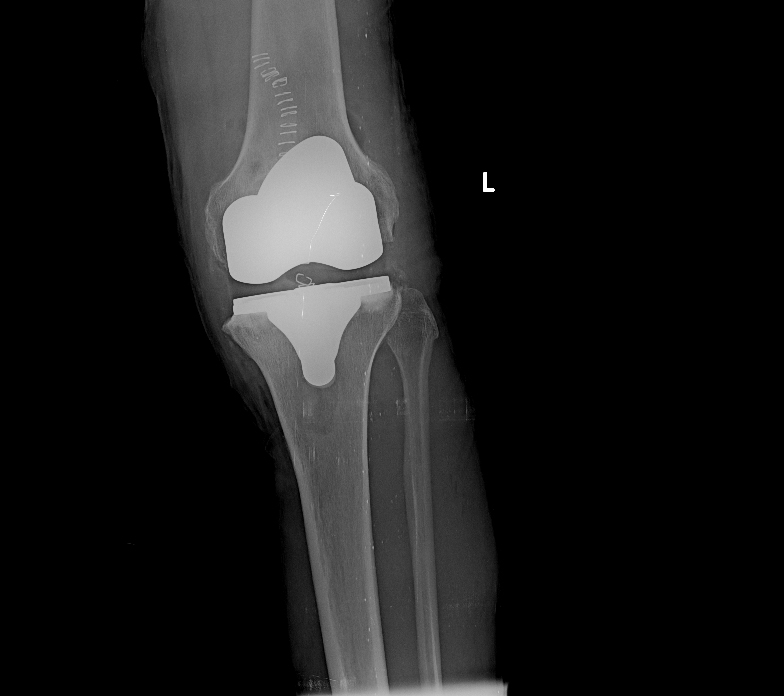

Η ολική αρθροπλαστική γόνατος ελάχιστης επεμβατικότητας γίνεται συνήθως με μέση προσπέλαση ή subvastus προσπέλαση, ανάλογα με την προτίμηση του χειρουργού. Με ειδικά εργαλεία-οδηγούς διαμορφώνεται ο μηρός, η κνήμη και η επιγονατίδα ώστε να αφαιρεθεί ο χόνδρος και το υποχόνδριο οστό. Κατόπιν, τοποθετούνται δοκιμαστικές προθέσεις, ώστε να εκτιμηθεί το εύρος κίνησης της άρθρωσης και –αν χρειάζεται- να χαλαρώσουν οι σύνδεσμοι του γόνατος.

Στη συνέχεια, ο χειρουργός τοποθετεί τις τελικές προθέσεις που εφαρμόζουν συνήθως με τη συνδρομή ειδικού ιατρικού τσιμέντου και επιβεβαιώνει τον αρχικό σχεδιασμό. Διενεργείται αιμόσταση και σχολαστικός καθαρισμός του γόνατος, πριν ολοκληρωθεί η επέμβαση με τη συρραφή του χειρουργικού τραύματος.